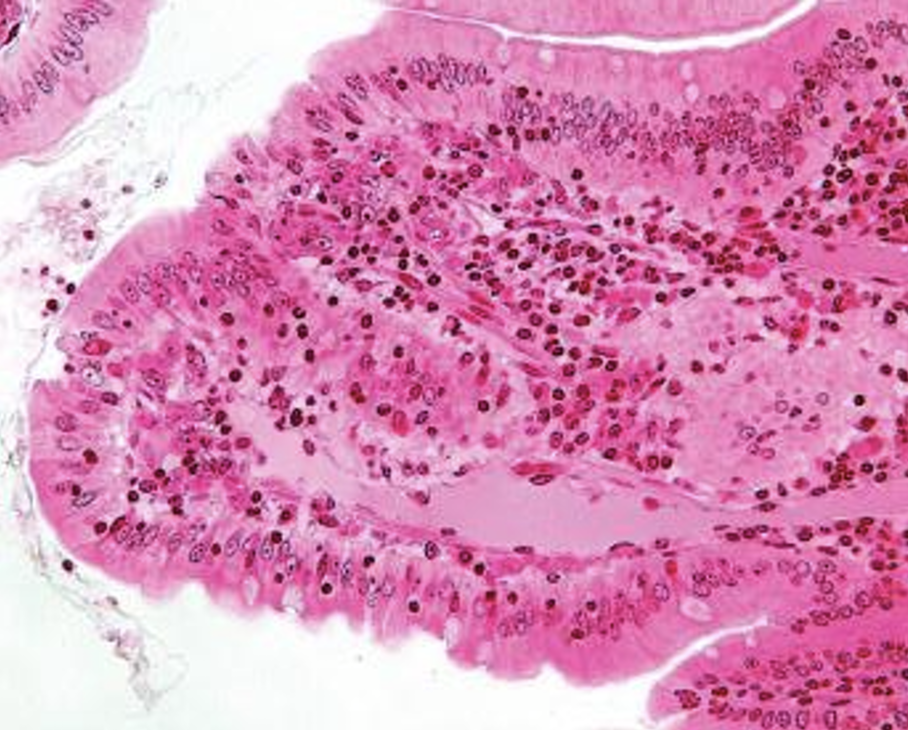

What system is this? And what are its features?

Lymphatic Sys: collects fluid form CT, bv w/ Endothelium, no RBCs = pink